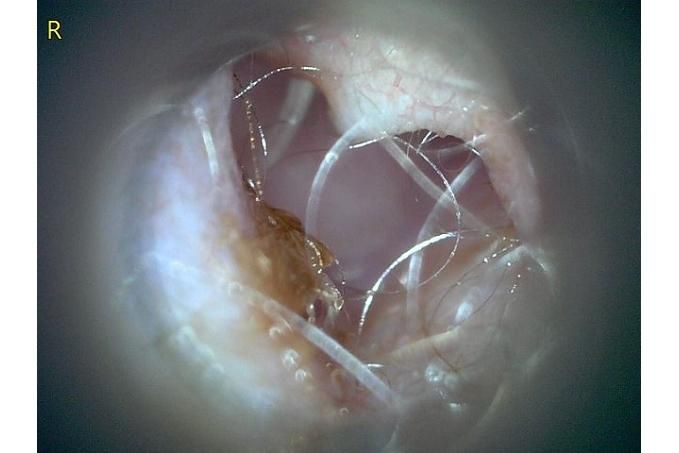

오늘 낮과 방금 5분전에 일어난 일인데요.. 강아지 귀질환 중에.. 옷입히고나서 귀를 바닥에 대고 비비거나, 귀에 통증을 호소하면서 잠깐 비틀비틀 걷는 경우 이런 경우 대체 뭘까요? 외이염일때도 이럴수도 있을까요? 아니면 중이염 내이염일지.. 한 2~3분정도 통증을 호소하다 지금은 또 정상이 됬는데 옷입을때만 옷의 목카라 부분이 귀에 닿을때 문제가 되는 느낌입니다. 평상시엔 가끔 양쪽 귀를 긁거나 귀를 자주 터는 정도입니다. 특이사항은 오른쪽귀 솜 돌돌 말아 귀안에 넣어줘도 비명을 지르며 엄청 아파하는데(작년11월경) 왼쪽은 안아파합니다)

그리고 용종이라고 코멘트 달아주셔서 저 검이경 사진 찍은곳에 물어보니 용종은 아니라고합니다.

저 부분 용종 아니라합니다

제가 가장 알고싶은점은. 저렇게 옷깃에 귀가 시쳐도 아파할정도면 이게 외이염일까요 중이염일까요 내이염일까요? 얼마나 아픈지 옷한번 얇은 내복 평상시 입던거 입히면 입히고 나서 바로 온집을 돌아다니면서 바닥에 귀를 대고 정신나간애처럼 비비고 비틀비틀 걷습니다 그러다가 2~3분후 다시 정상으로 돌아옵니다

(근데 또 귀를 조물락 조물락 만져도 안아파합니다, 다만 솜을 길게 해서 넣으면 솜만 넣어도 아파합니다 특히 오른쪽요 왼쪽은 안아파합니다)